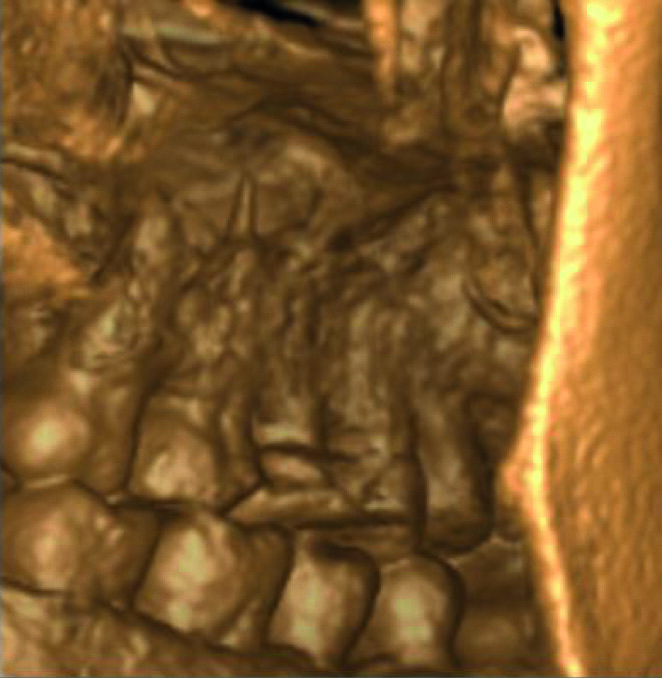

Un patient avait été adressé au cabinet en raison de problèmes associés à la fracture d’une lime. Il était pilote de ligne et se plaignait d’écoulements nasaux purulents lorsqu’il était en vol. La radiographie pré-opératoire (Fig. 1) a distinctement montré la présence de deux fragments d’une lime fracturée dans les canaux mésiaux et d’un cône traversant l’apex de la racine palatine. Après l’imagerie CBCT avec iCAT, il est apparu clairement que le sinus gauche était presque totalement rempli de liquide inflammatoire (Fig. 2) et que le cône présent dans le canal palatin pénétrait dans le sinus. Sur l’image de reconstruction multi planaire (MPR), nous pouvions également distinguer les deux fragments de lime fracturée dans les deux canaux mésiaux (Figs. 3 et 4) et aussi un autre fragment dans le sinus sans aucun contact avec le canal (Fig. 5). L’utilisation de différents filtres nous a permis de visualiser les fragments de lime (Figs. 6–9), ainsi que l’inflammation et le fragment de lime fracturée à l’intérieur du sinus. Nous avons également mieux perçu la position du cône qui émergeait du canal palatin et pénétrait dans le sinus.

Le plan de traitement a consisté à tenter de résoudre le problème par une approche classique et, au besoin, par une microchirurgie, en vue de conserver la dent. J’ai pu retirer le cône de la racine palatine a l’aide de limes H (Hedstrom) mais il était impossible de contourner les fragments de lime présents dans la racine mésiale, ou même de les atteindre avec des inserts ultrasoniques. Je me suis résolu à ne pas en faire trop afin de ne pas créer un nouveau problème, tel qu’une perforation de la paroi canalaire, et j’ai décidé de sceller les canaux (Fig. 10). La décision de traiter les canaux mésiaux par une approche chirurgicale a été prise immédiatement. J’ai sectionné 3 mm de la racine mésiale à l’aide d’une pièce à main Impact Air (SybronEndo), ce qui m’a donné une vue directe sur la membrane de Schneider, de laquelle le troisième fragment dépassait à peine (Figs. 11 et12). Je suis parvenu a le saisir délicatement et à l’extraire (Fig. 13). La figure 14 montre la situation post-opératoire, après la fin de la préparation à retro des canaux mésiaux.